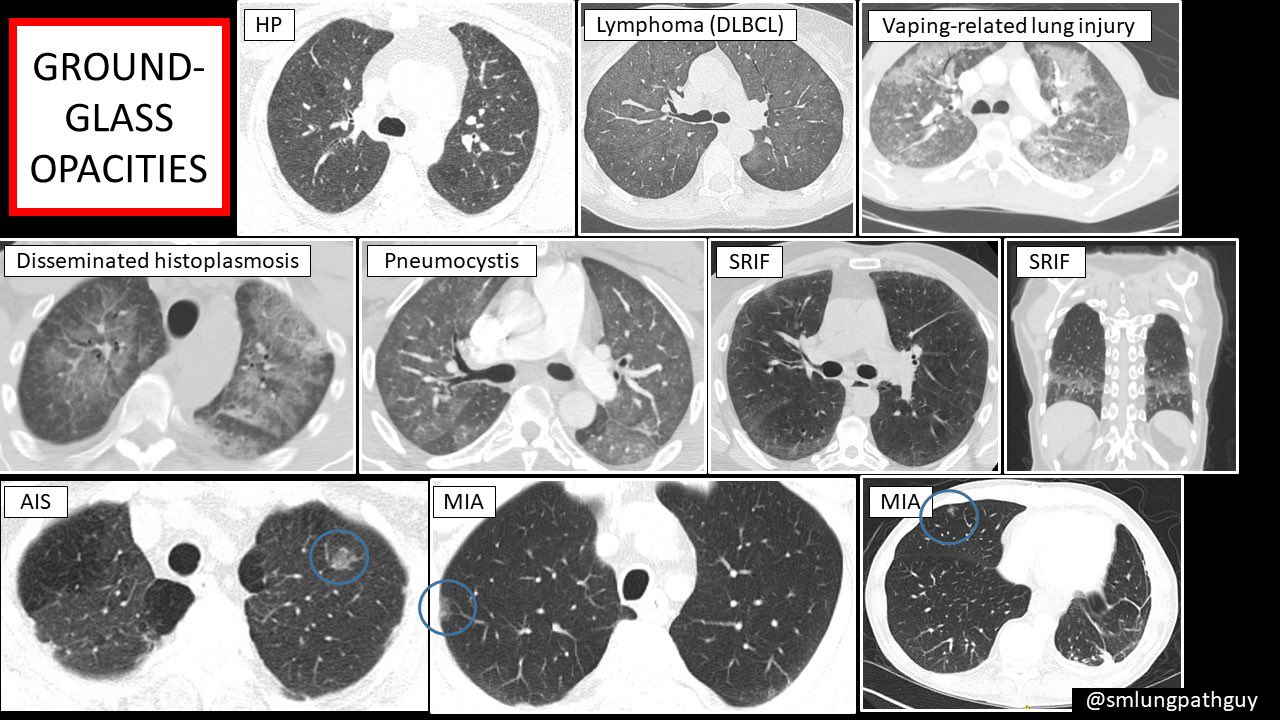

Sanjay Mukhopadhyay on Twitter "I made these slides to explain ground